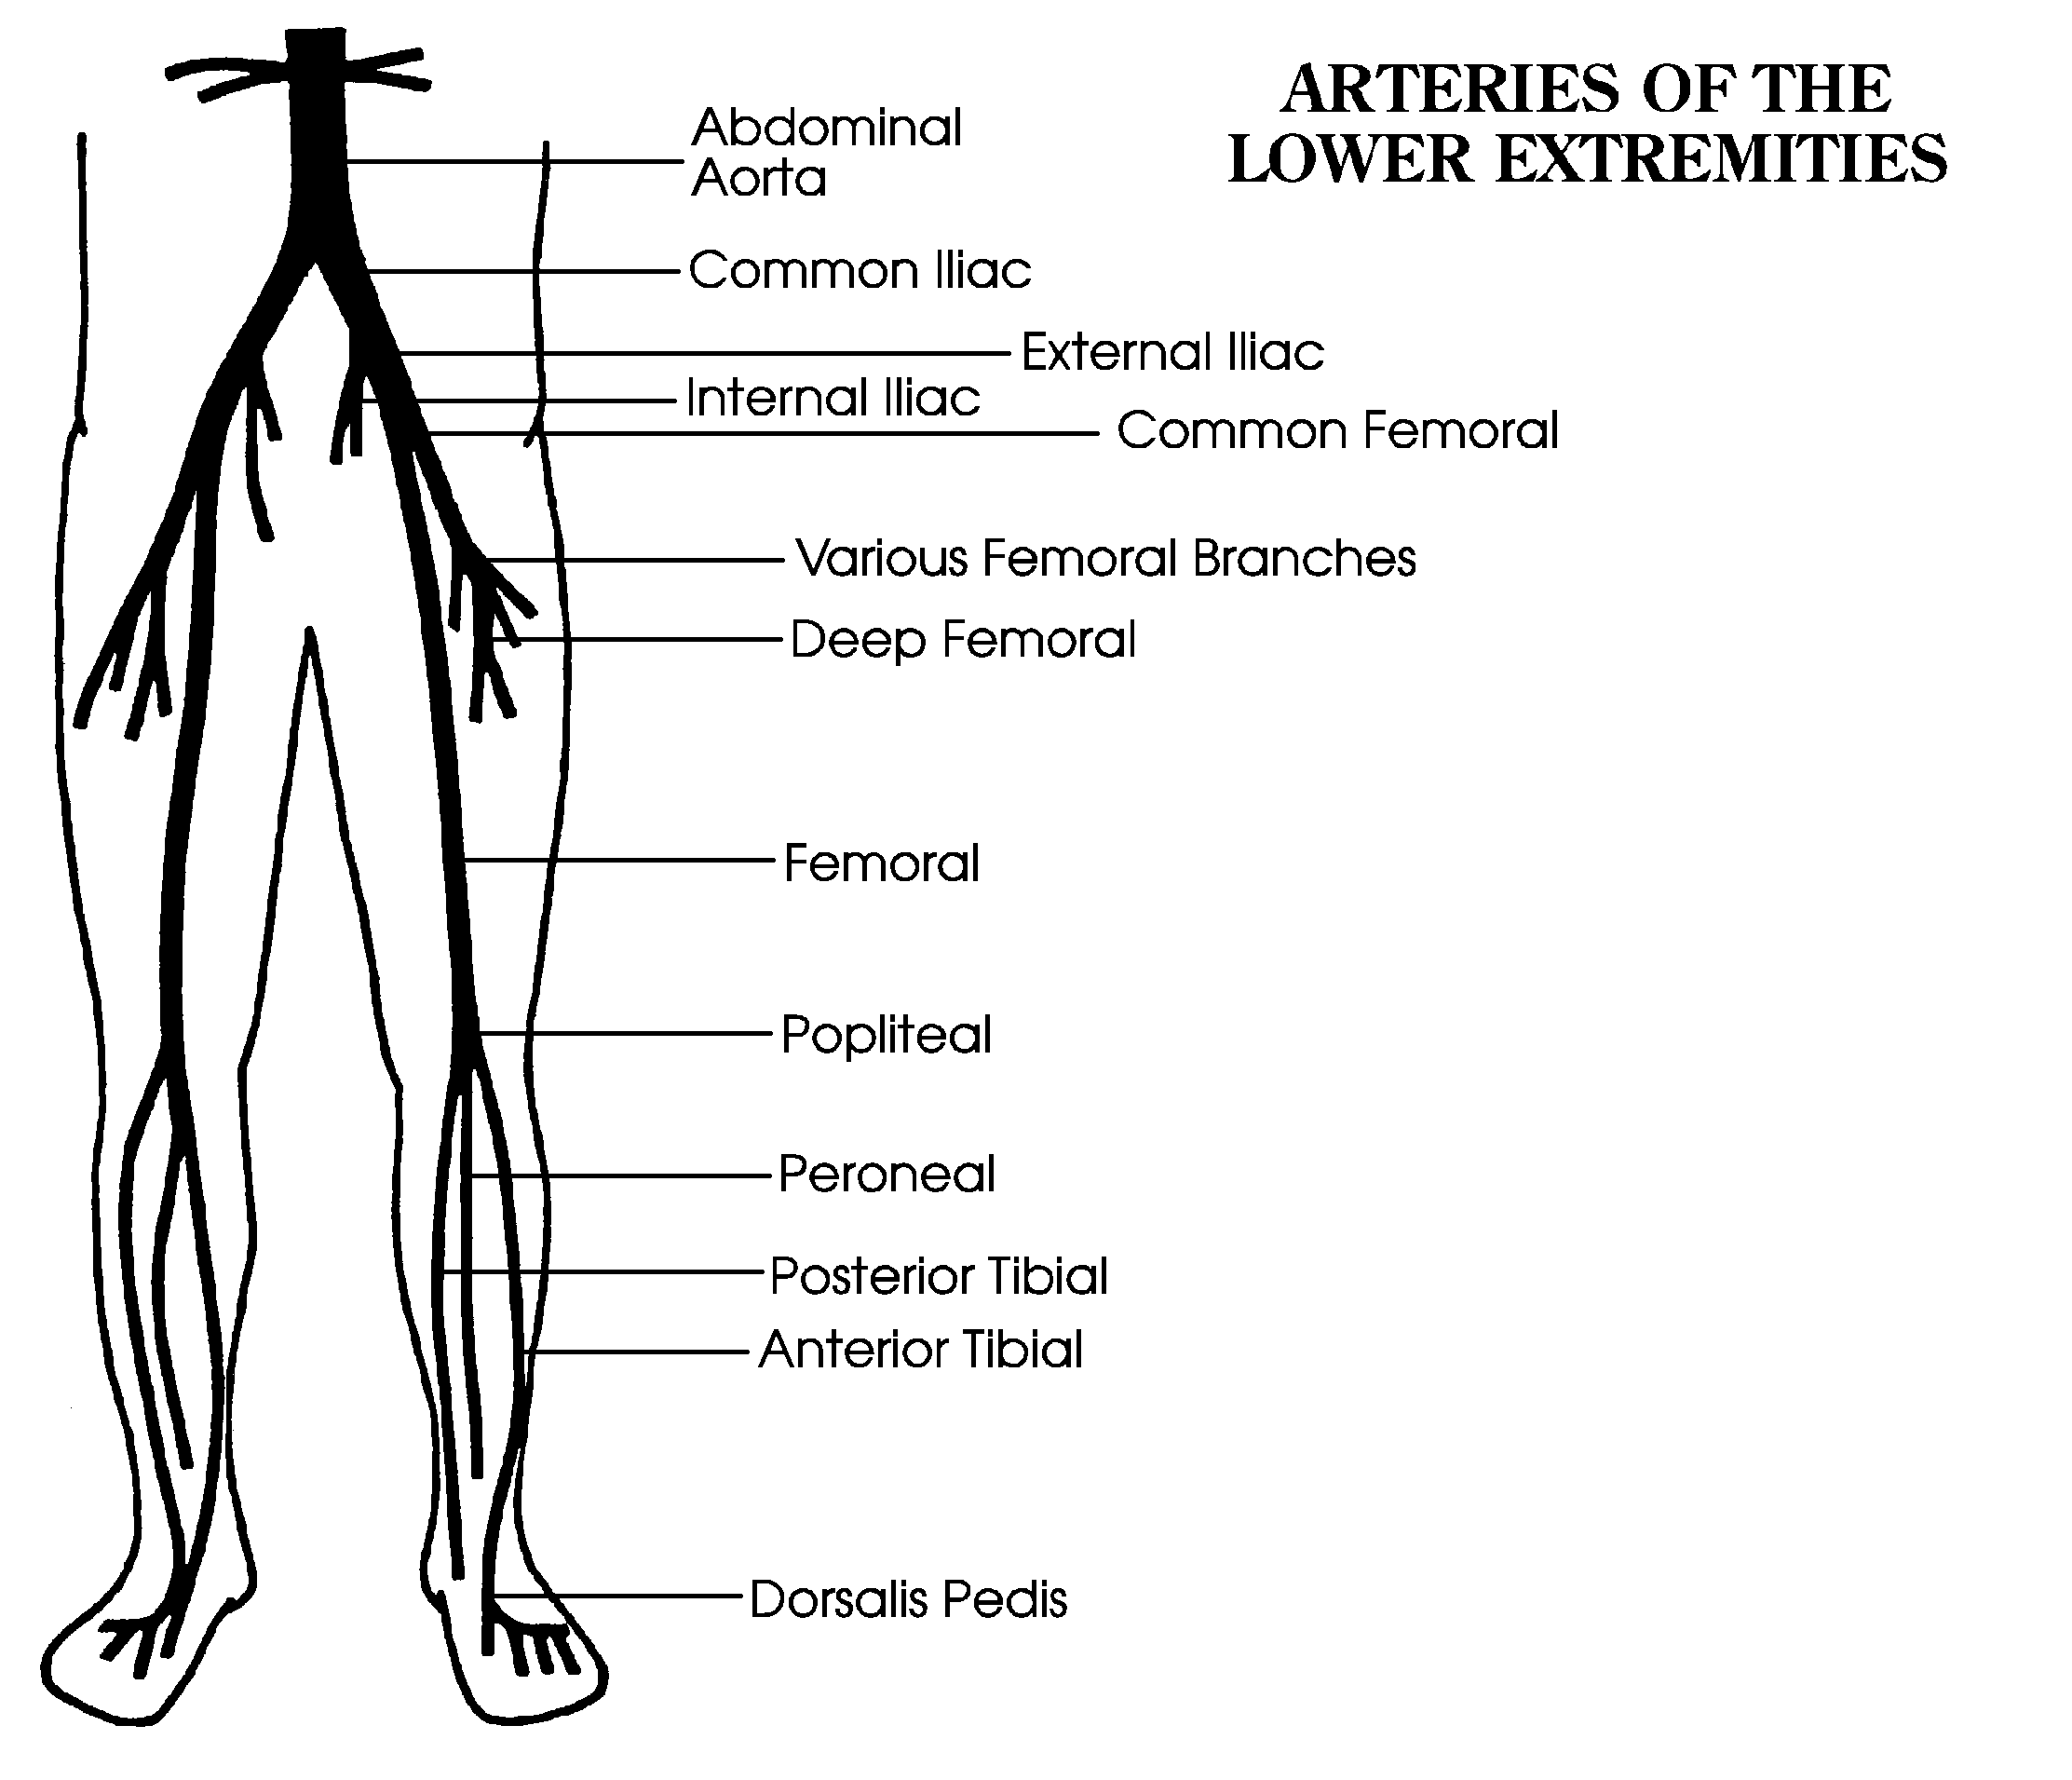

Albums showcases captivating images of a deposit of plaque within the arterial wall galleryz.online

a deposit of plaque within the arterial wall

a deposit of plaque within the arterial wall at